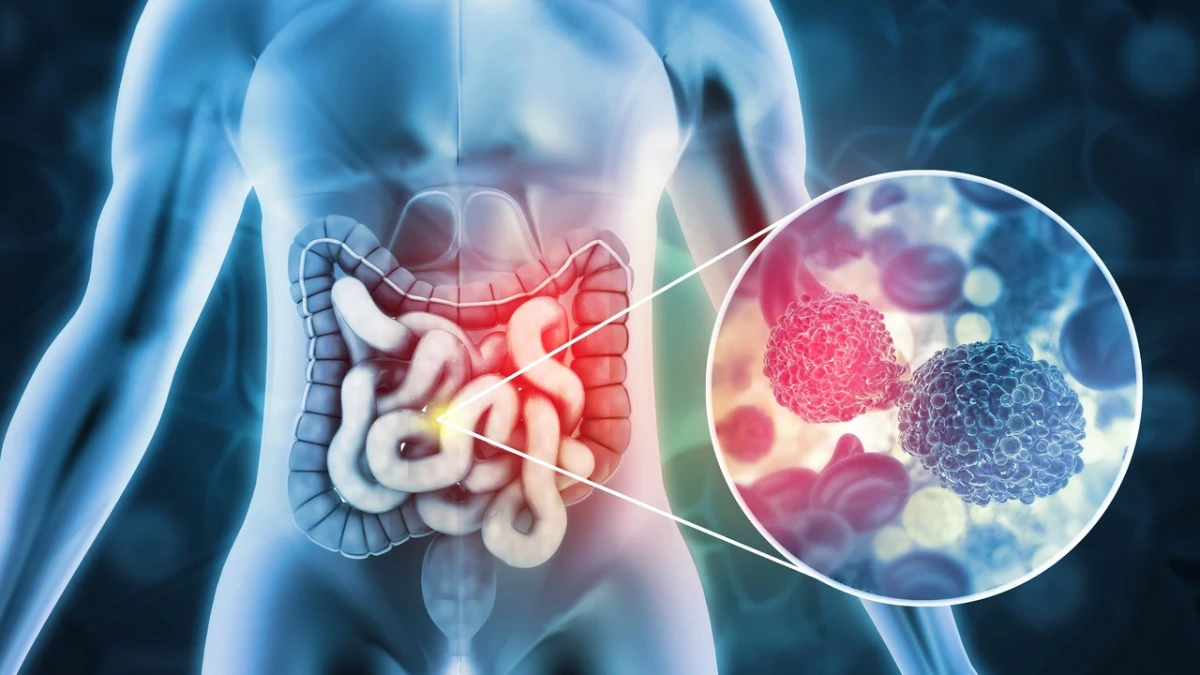

۳. سرطان روده بزرگ

سرطان روده بزرگ معمولاً در افراد بالای ۵۰ سال شایع است و میتواند با تغییر سبک زندگی و غربالگری زودهنگام کنترل شود.

علائم اولیه:

- تغییر در عادتهای روده، مثل یبوست یا اسهال مداوم.

- خون در مدفوع یا مشاهده رنگ غیرطبیعی آن.

- کاهش وزن بدون دلیل و خستگی غیرمعمول.

- درد شکم یا نفخ مداوم.

- احساس عدم تخلیه کامل روده بعد از اجابت مزاج.

نکات کاربردی:

- کولونوسکوپی منظم برای افراد بالای ۵۰ سال یا با سابقه خانوادگی توصیه میشود.